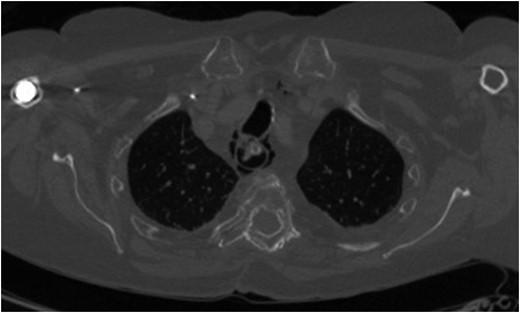

For management of this oesophageal perforation and definitive management of her gastric perforation, the patient was referred to the authors’ unit, a tertiary referral centre for upper GI surgery. In the first instance, a water-soluble contrast swallow was performed to assess the status of the oesophageal perforation. This demonstrated no leak of contrast (Fig. 3) and therefore a diagnostic endoscopy under general anaesthesia was performed in order to assess the cervical oesophagus and also the known gastric perforation. This endoscopy demonstrated a healed oesophageal perforation but persistent gastric perforation with established cavity (Fig. 4) containing an existing transabdominal Robinson drain. The cavity was felt to be of a size likely to heal without the need for further negative pressure vacuum therapy, so a T-tube was placed across it. The established track of the existing abdominal drain was used to guide placement of the T-tube. A nasojejunal feeding tube was placed under vision.

Endoscopic photograph showing perforation of the posterior gastric wall with established cavity.